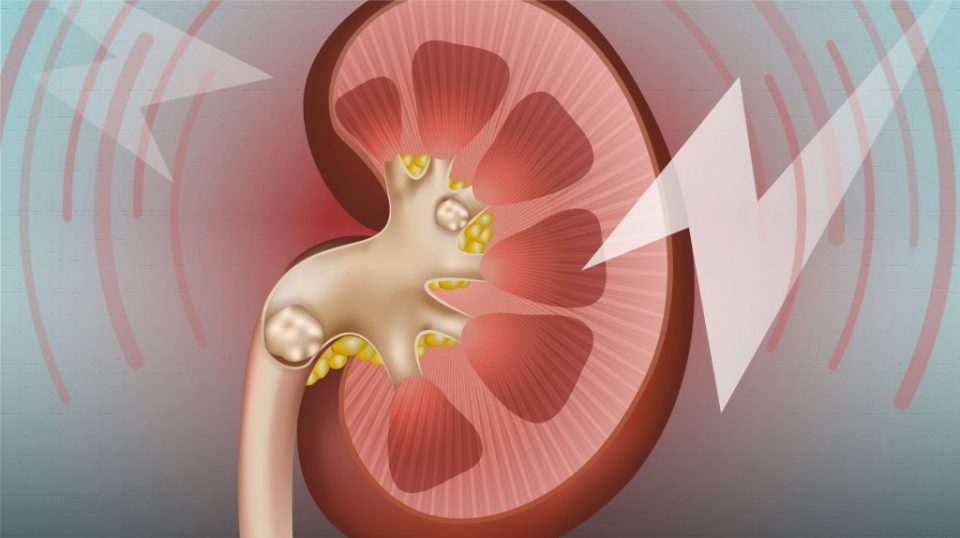

Kidney Stone problem: ਅੱਜ-ਕੱਲ੍ਹ ਪੱਥਰੀ ਹੋਣਾ ਹੁਣ ਇਕ ਆਮ ਸਮੱਸਿਆ ਬਣ ਗਈ ਹੈ। ਜ਼ਿਆਦਾਤਰ ਲੋਕ ਇਸੇ ਬੀਮਾਰੀ ਦਾ ਸ਼ਿਕਾਰ ਹੋ ਰਹੇ ਹਨ। ਪੱਥਰੀ ਵੀ ਕਈ ਤਰ੍ਹਾਂ ਦੀ ਹੋ ਸਕਦੀ ਹੈ ਜਿਵੇਂ ਕਿ ਪਿੱਤੇ ਦੀ ਪੱਥਰੀ, ਗੁਰਦੇ ਦੀ ਪੱਥਰੀ, ਬਲੈਡਰ ਦੀ ਪੱਥਰੀ ਆਦਿ। ਅਜਿਹੇ ‘ਚ ਆਮ ਤੌਰ ‘ਤੇ ਆਪਰੇਸ਼ਨ ਦੀ ਸਲਾਹ ਦਿੱਤੀ ਜਾਂਦੀ ਹੈ। ਇਹ ਕਿਸੇ ਵੀ ਉਮਰ–ਵਰਗ ਦੇ ਵਿਅਕਤੀ ਨੂੰ ਹੋ ਸਕਦੀ ਹੈ। ਇਸ ਨਾਲ ਢਿੱਡ ਜਾਂ ਪਿੱਠ ਵਿੱਚ ਕਾਫ਼ੀ ਜ਼ਿਆਦਾ ਦਰਦ ਹੁੰਦਾ ਹੈ। ਪੱਥਰੀ ਕੋਈ ਬੀਮਾਰੀ ਨਹੀਂ, ਸਗੋਂ ਸਾਡੀ ਗ਼ਲਤ ਜੀਵਨ–ਸ਼ੈਲੀ (ਲਾਈਫ਼–ਸਟਾਈਲ) ਦੀ ਦੇਣ ਹੈ, ਜਿਸ ਕਾਰਨ ਪੱਥਰੀ ਜਿਹੀ ਸਮੱਸਿਆ ਕਿਸੇ ਨੂੰ ਵੀ ਝੱਲਣੀ ਪੈ ਸਕਦੀ ਹੈ।